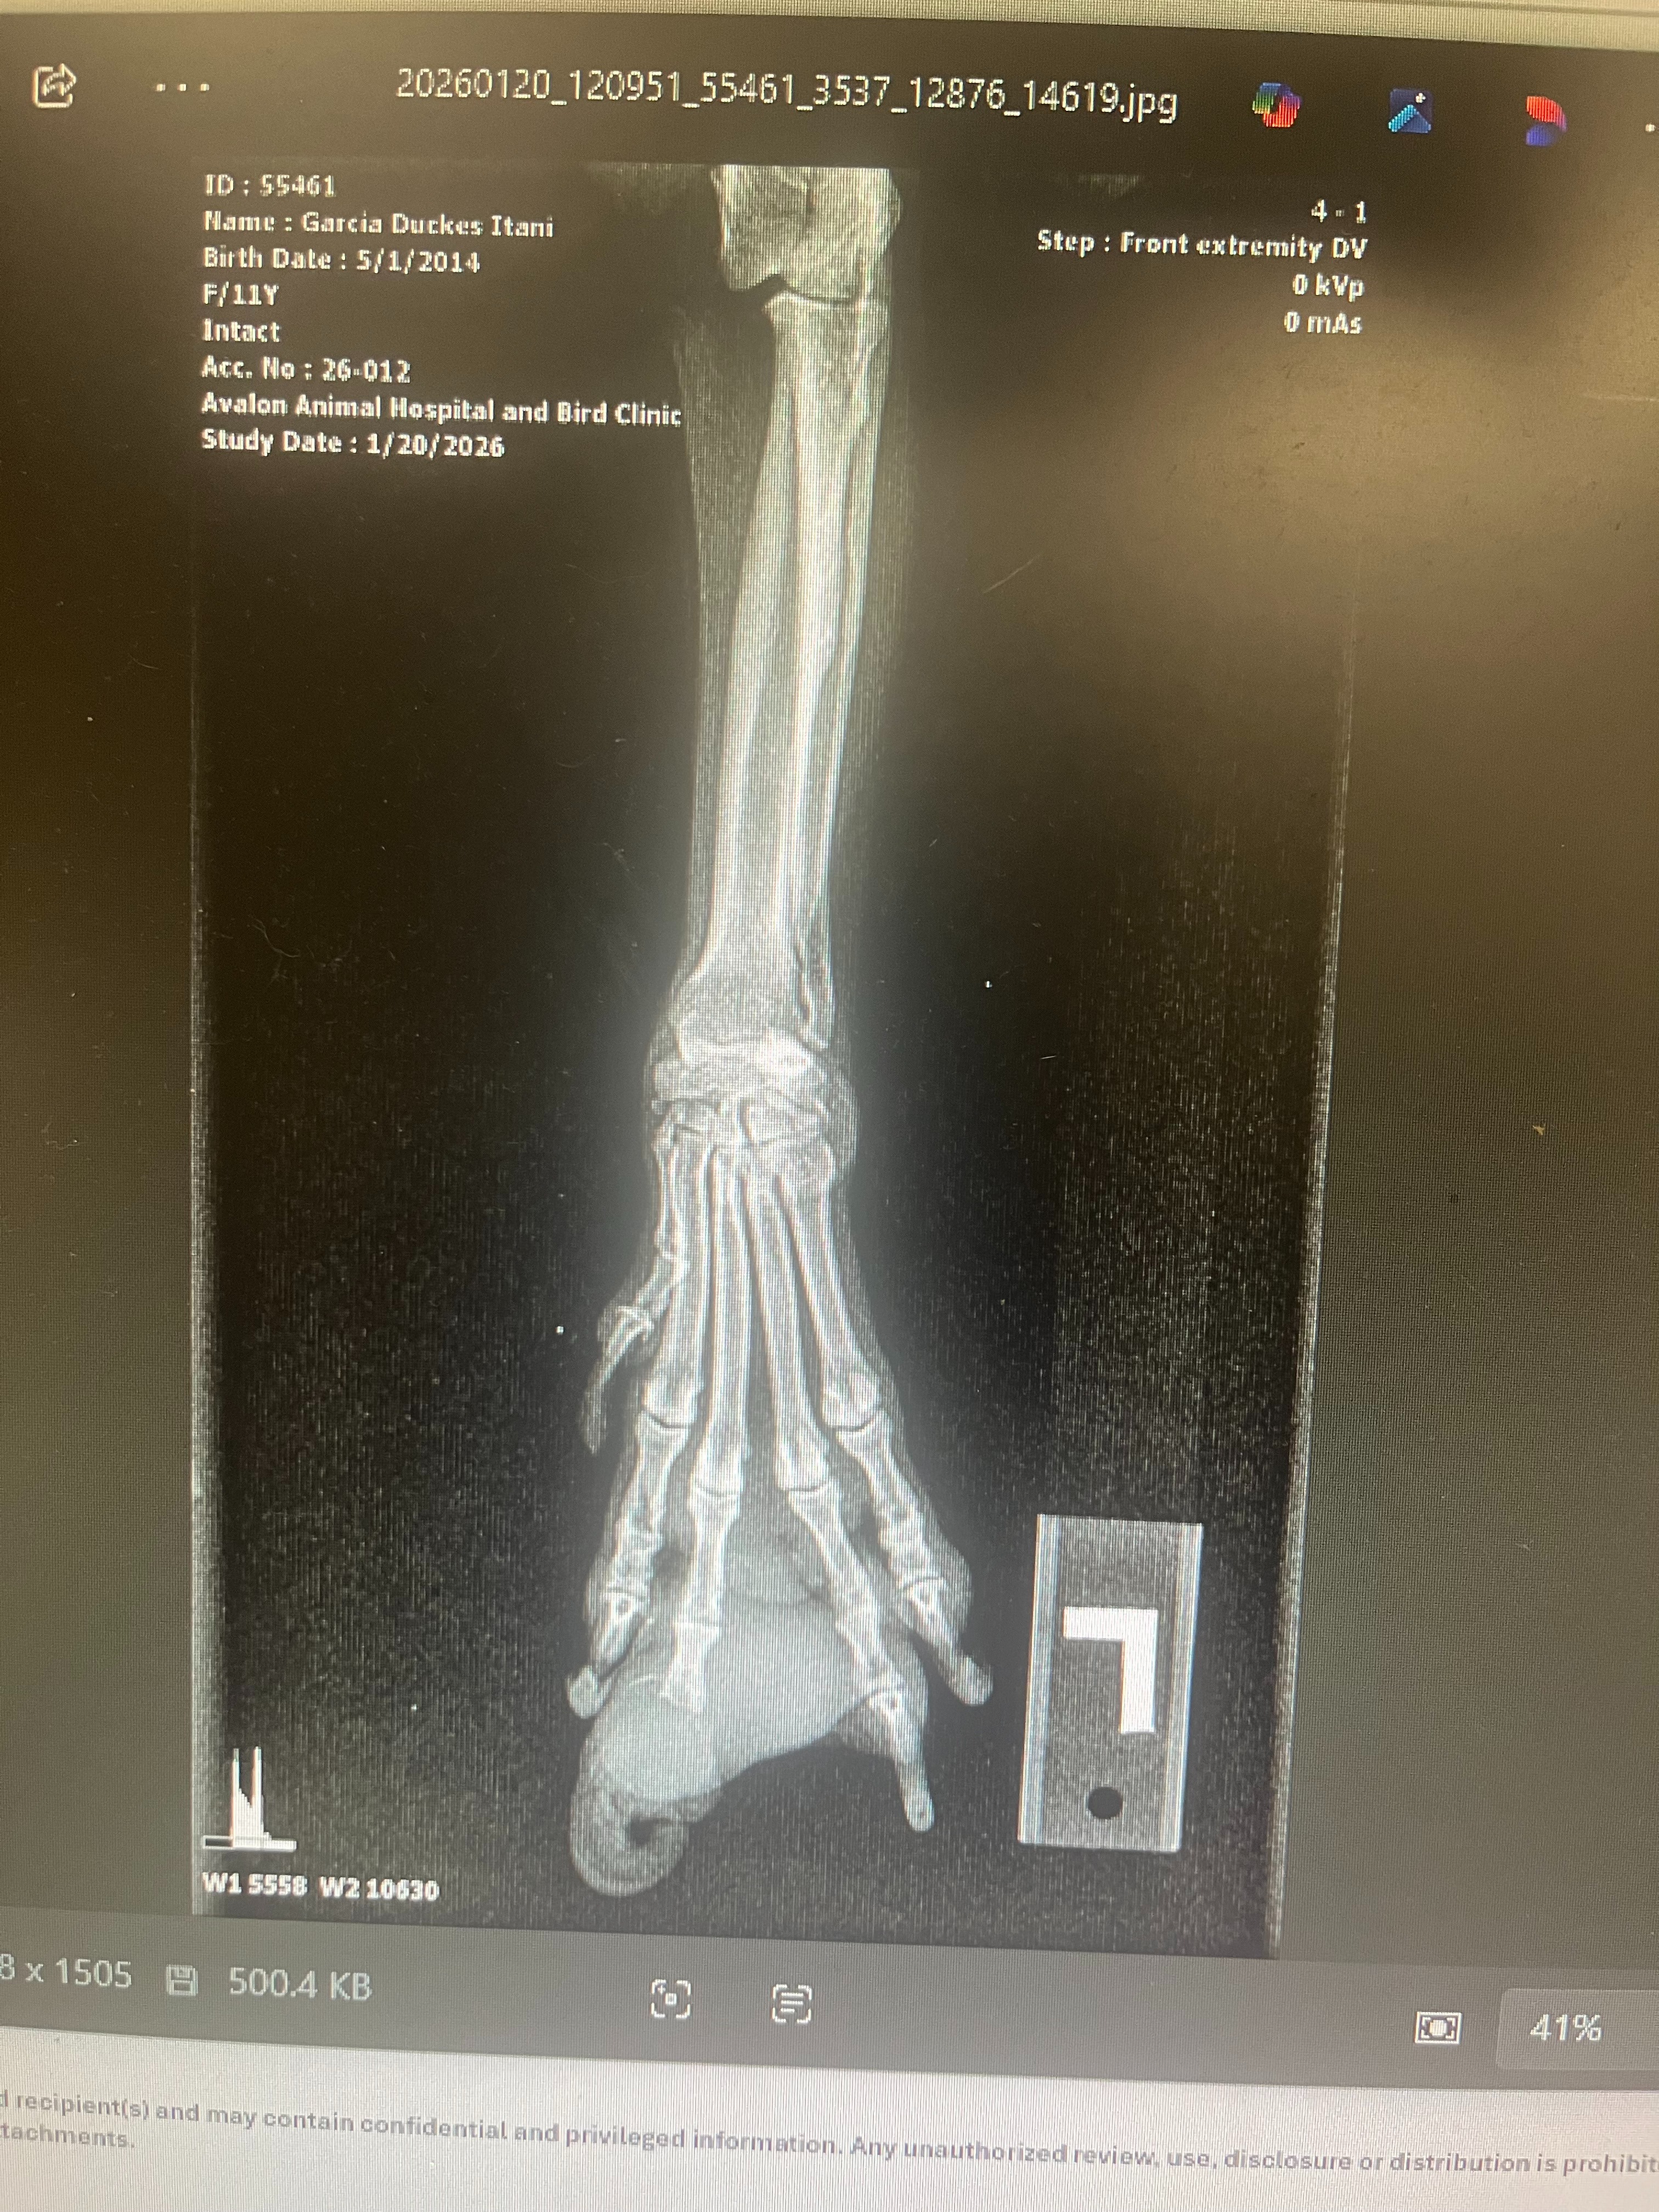

Hello, My family and I are starting this go fund me to try to save our dog. This is Duke He’s 12 years old and has been our loyal companion for so long. He’s currently growing a tumor on his paw. We’ve already had it examined and treated, which was very expensive, and now he needs surgery to fully take care of it.

Hi, I’m Duke I’m 12 years old and my paw has a tumor that needs surgery. My human has already done so much for me, and now we’re asking for a little help.